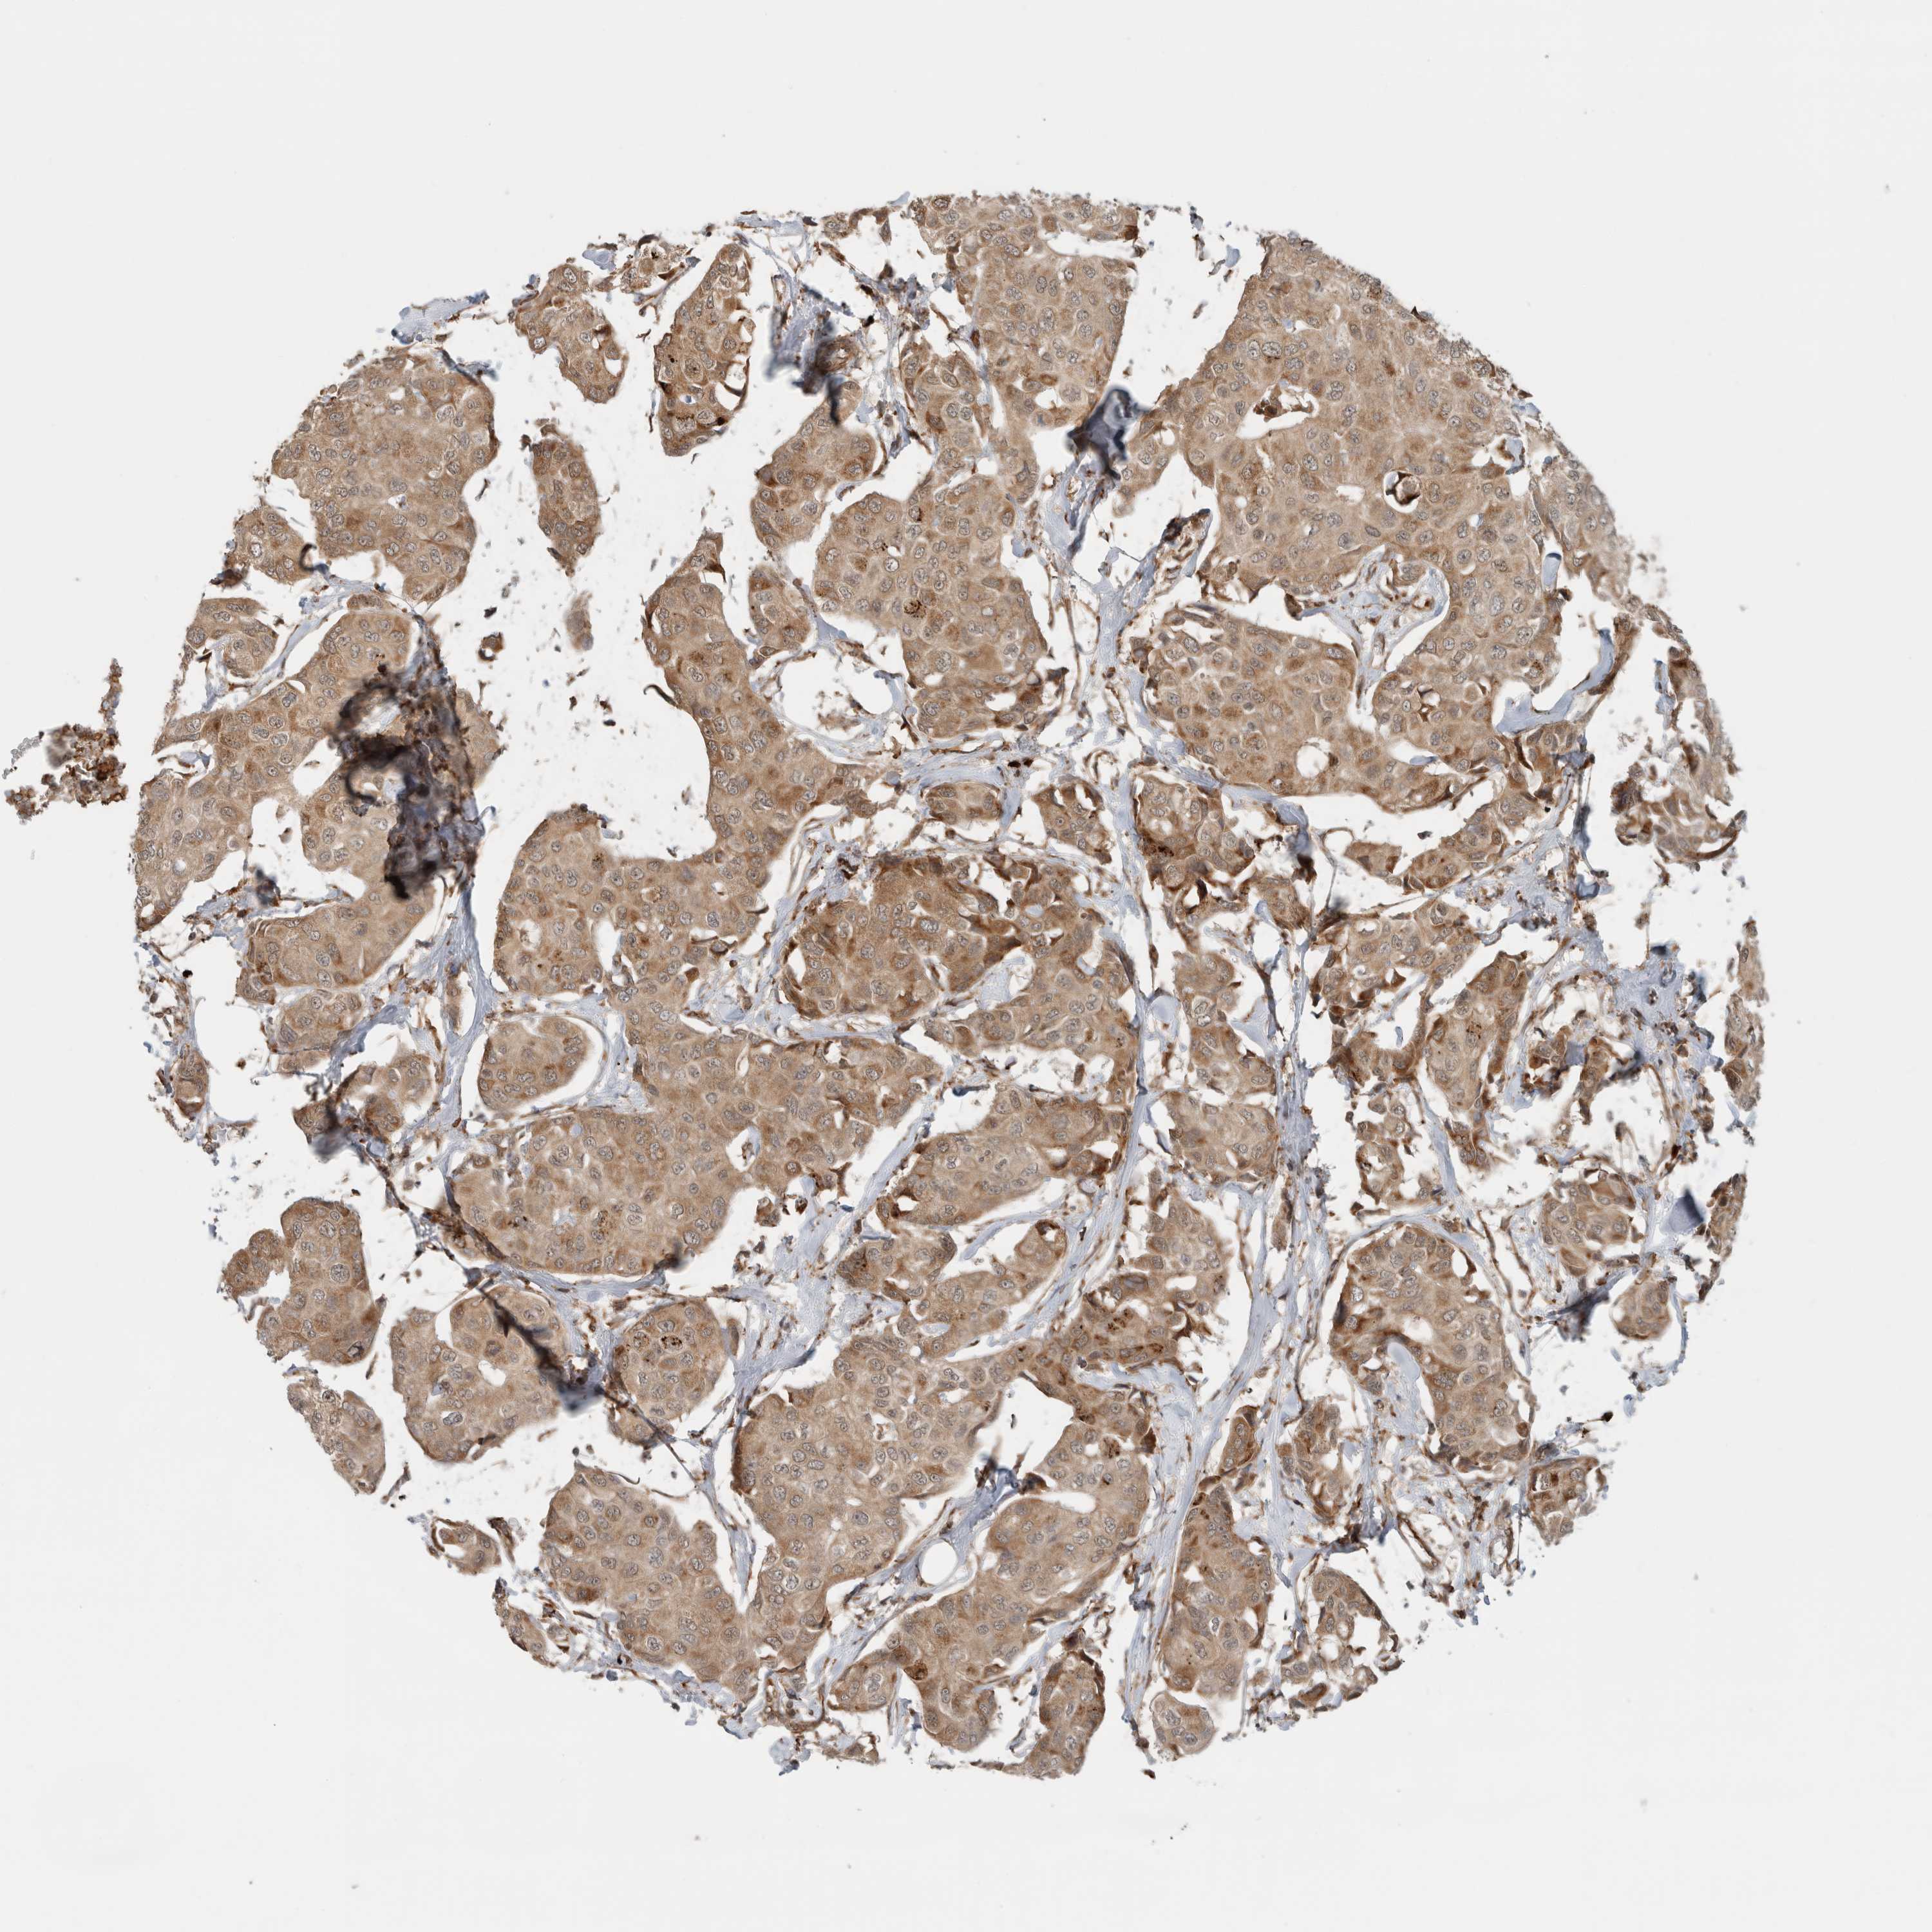

CANCER BREAST CANCER Show tissue menu

BRCA TCGA BRCA VALIDATION PROTEIN EXPRESSION